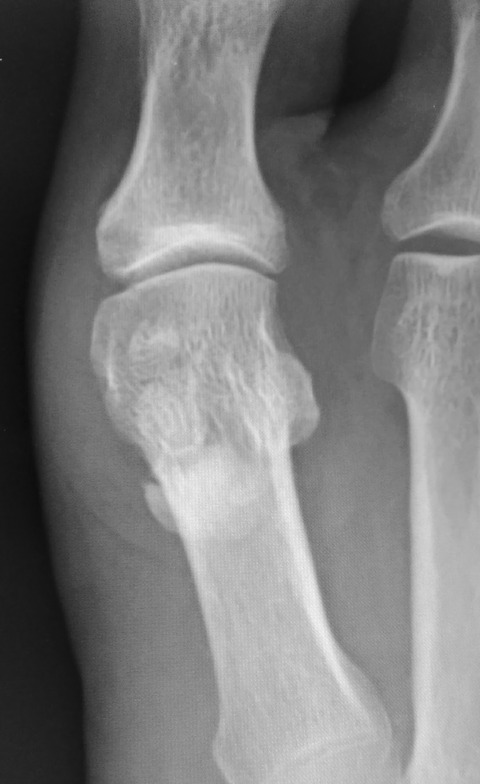

何の疑いもなく「痛風ですね」と言いそうになって、単純X線像を見てハッと息を飲みました。それが下の画像です。

正面像で2つの種子骨の下に何かクルミのような像を認めます。ただ、正面像では正直に言って見逃しかけました。

しかし、斜位像では、種子骨よりも中枢側にはっきりとした石灰沈着象を認めます。これは、痛風ではないかもしれない・・・。